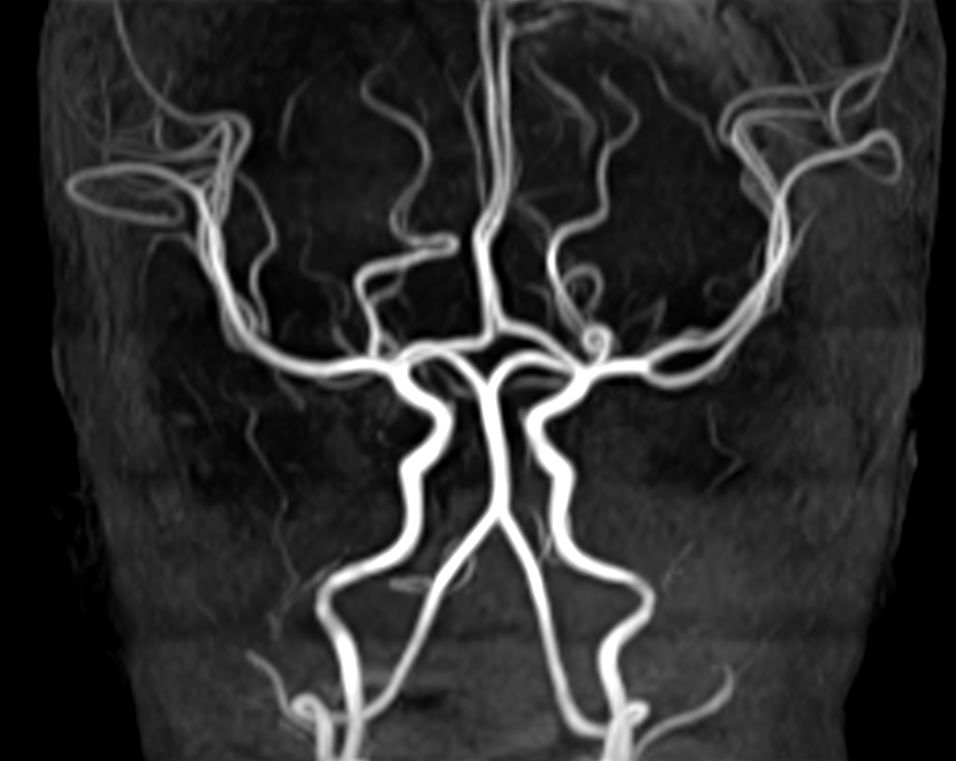

Axial 3D TOF (MIP)